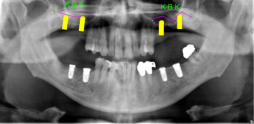

Beispiele für komplexe implantologische Versorgungen aus unserer Gemeinschaftspraxis

(Planung / Endversorgung -- als Röntgenaufnahmen)

C1